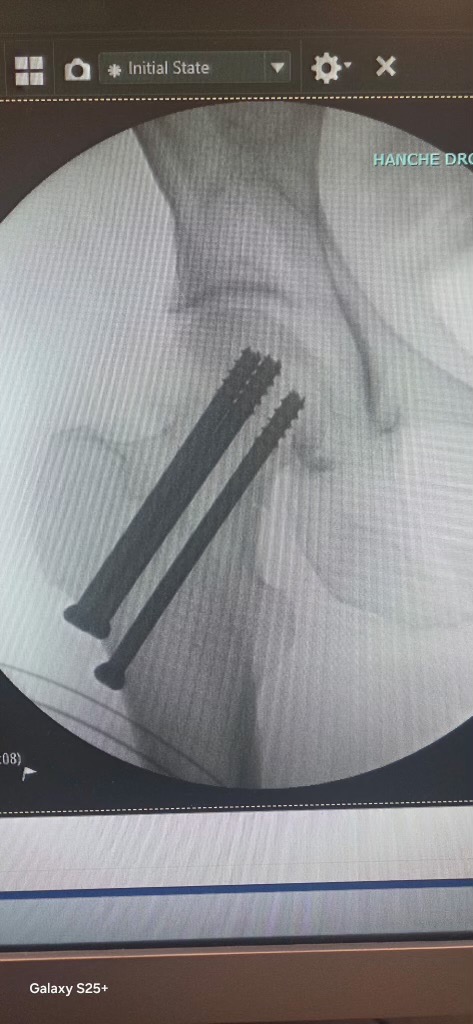

Tout a commencé par une inondation majeure dans son logement : le réservoir d’eau chaude du voisin du dessus a cédé, causant d’importants dégâts chez elle. Comme si ce n’était pas suffisant, le jour même de son anniversaire, Nathalie a fait une mauvaise chute qui lui a malheureusement causé une fracture de la hanche.